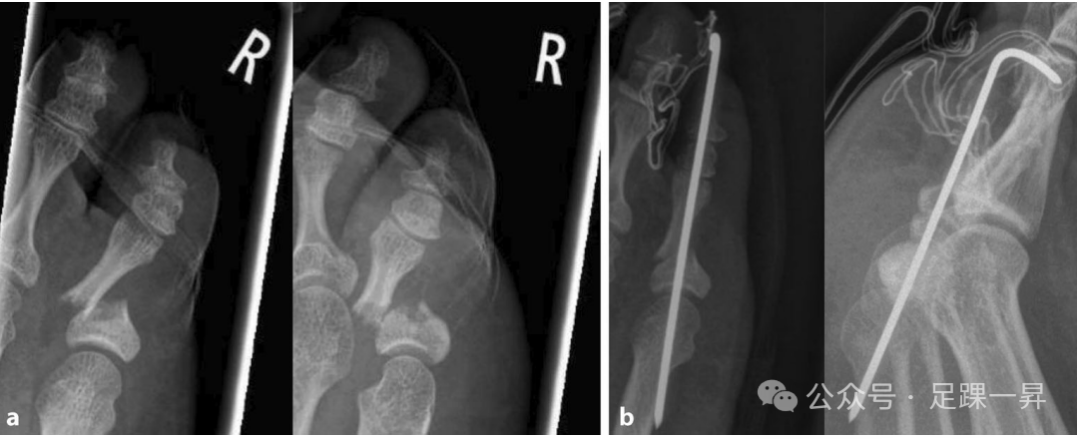

▲图示第5趾近端趾骨脱位性骨折。行闭合复位+克氏针固定术治疗,固定6周。a 术前X线片,b 术后第2天X线片。